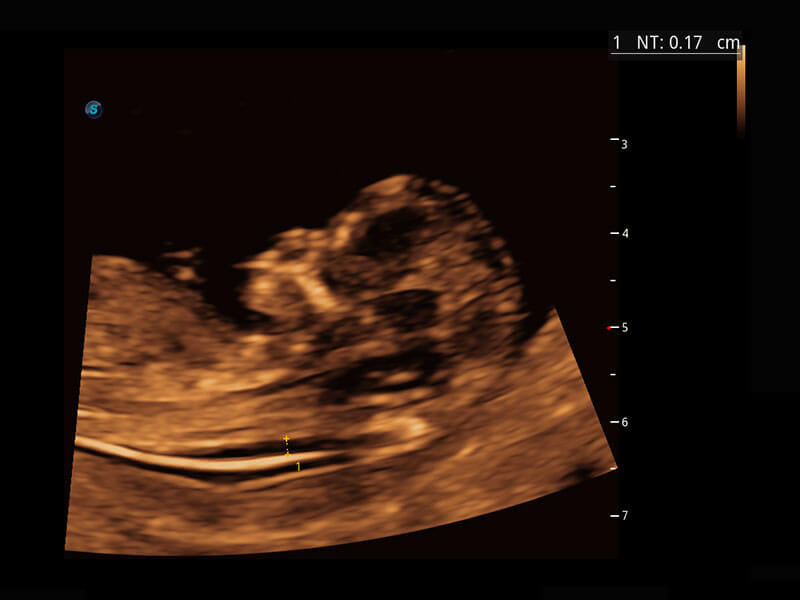

P60在胎儿早孕期超声筛查中为您带来优异的图像质量。

早孕-胎心

P60搭载一系列胎儿心脏成像技术,实现精细的胎儿心脏评估。

四腔切面